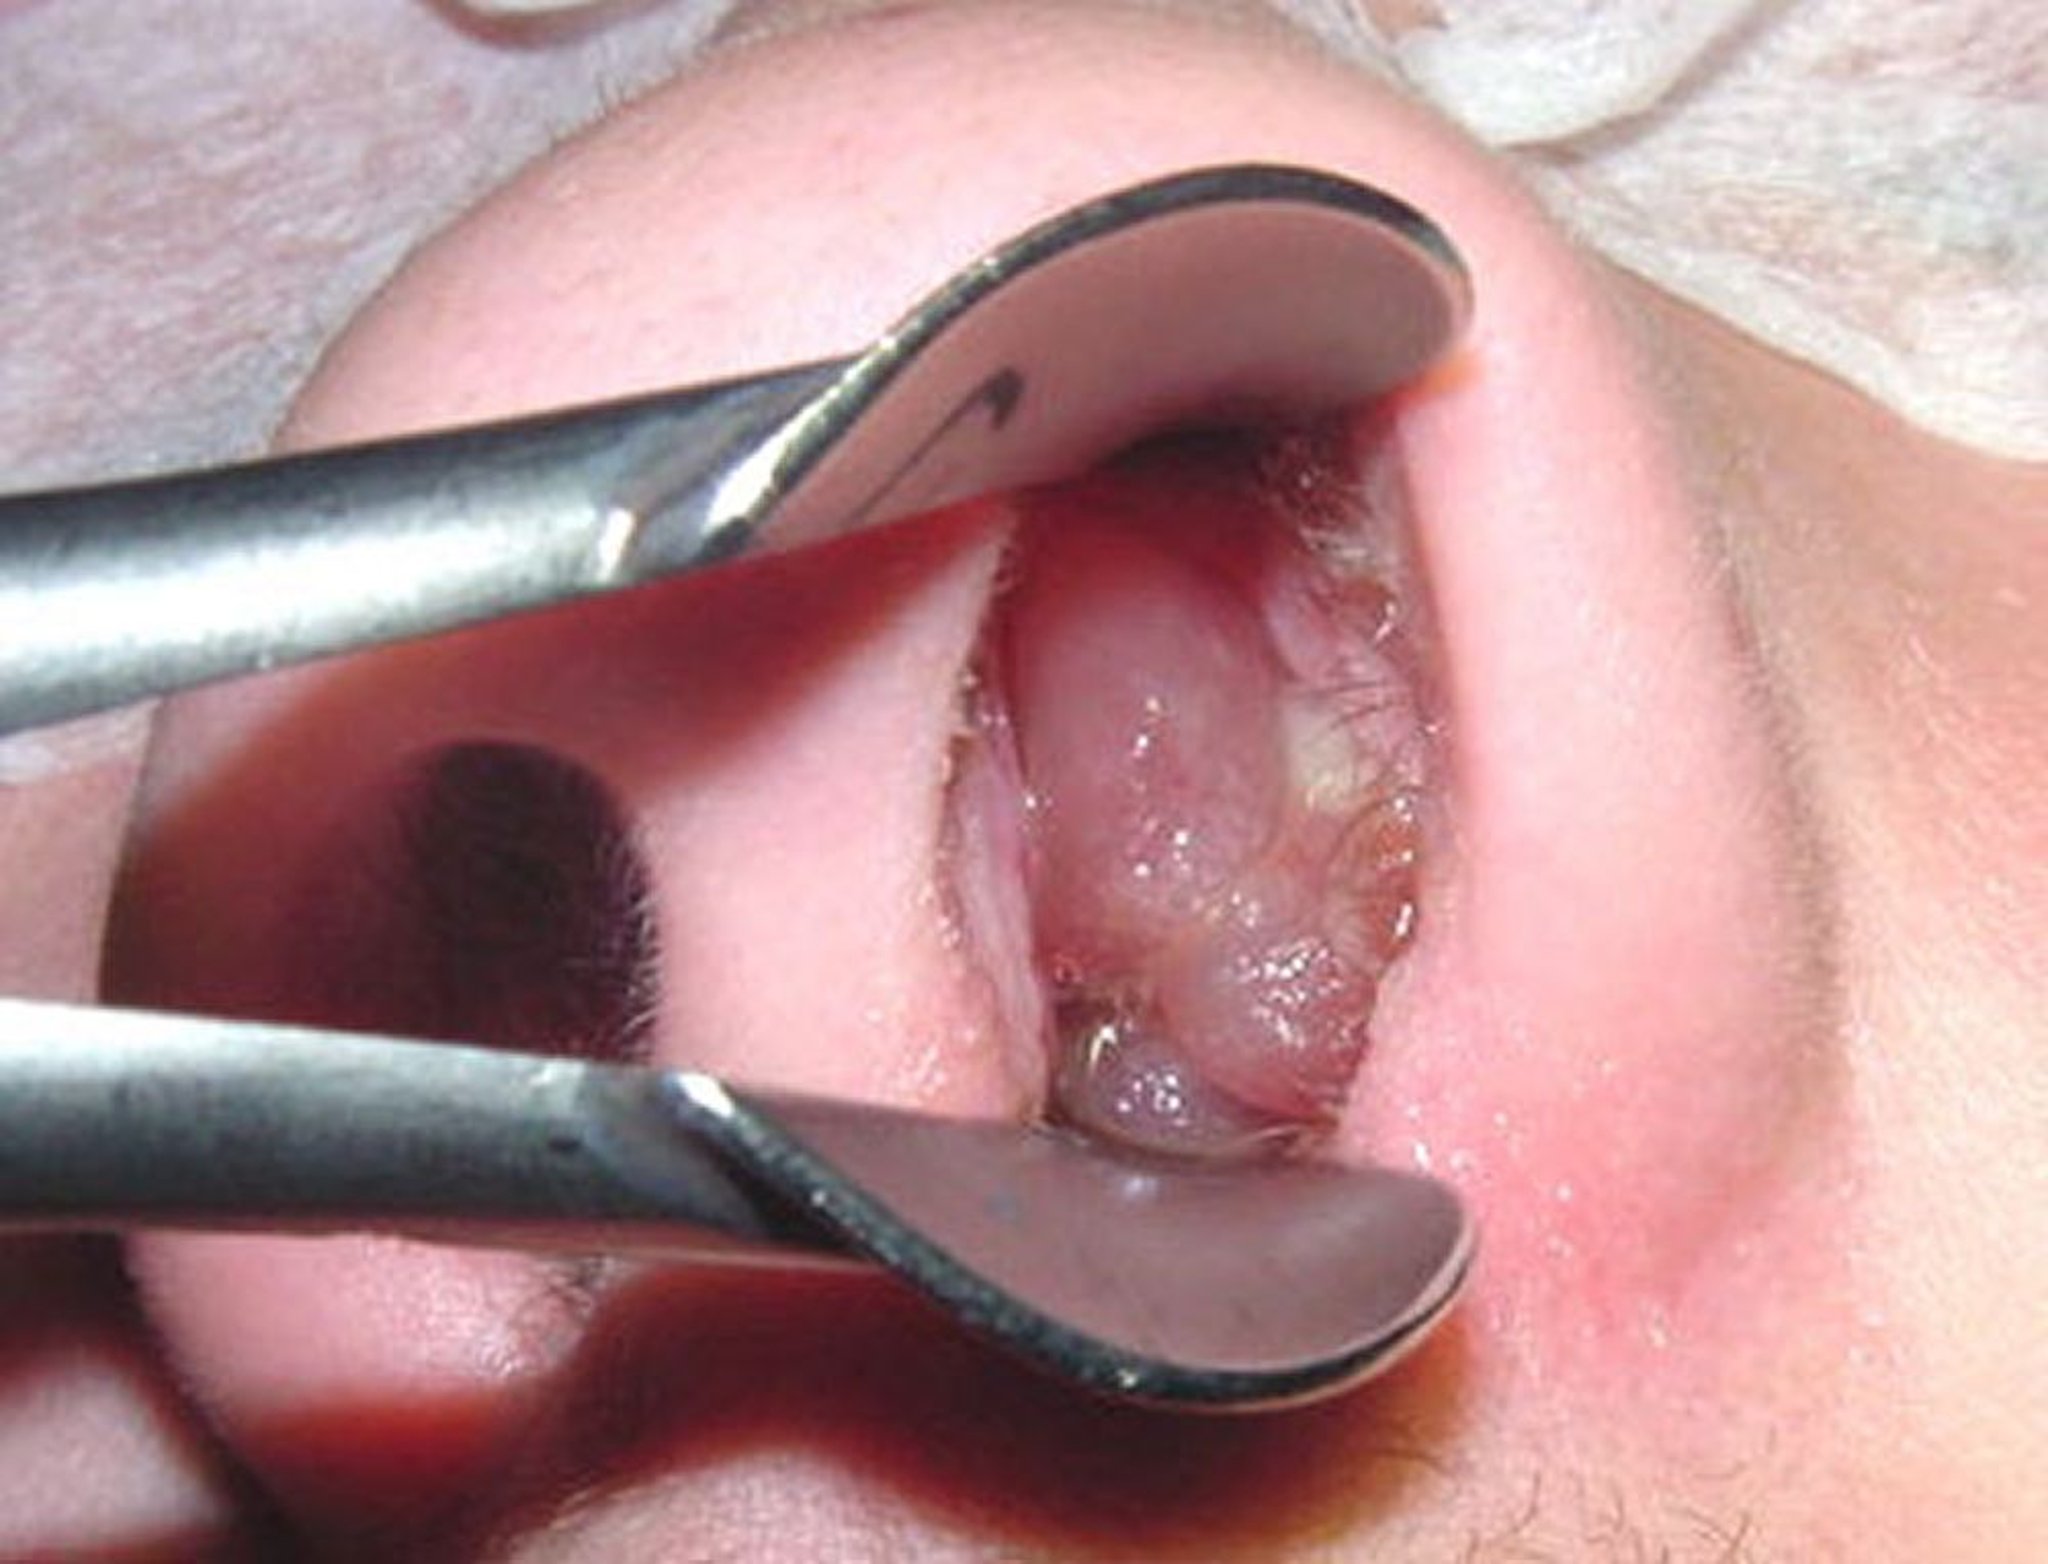

鼻茸

成熟

せいじゅく

した

はなたけ

は、

皮

かわ

をむいた

種

たね

なしブドウに

似

に

ていることがあります。

Image provided by Bechara Ghorayeb, MD.